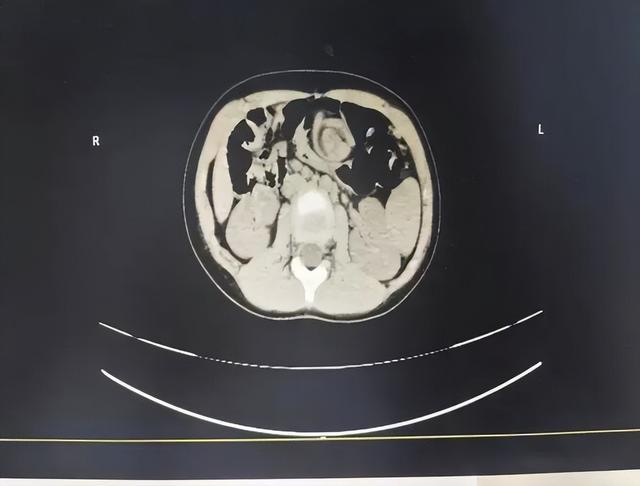

肛肠小儿外科主治医师杨文第一时间为可可办理住院,完善各项检查并予以补液治疗,腹部CT提示中腹部小肠及肠系膜血管呈漩涡征改变,高度怀疑中肠旋转不良伴肠扭转。

术中探查发现可可小肠顺时针扭转360度,肠系膜根部呈“钟摆样”悬吊,近端空肠淤血扩张。手术团队凭借精湛的微创技术,顺利松解肠管扭转、完成肠管复位,随后实施手术解除肠道狭窄、延长肠系膜根部,并将盲肠固定于右下腹,整个手术过程顺利,微创操作最大限度减少了可可的身体创伤。